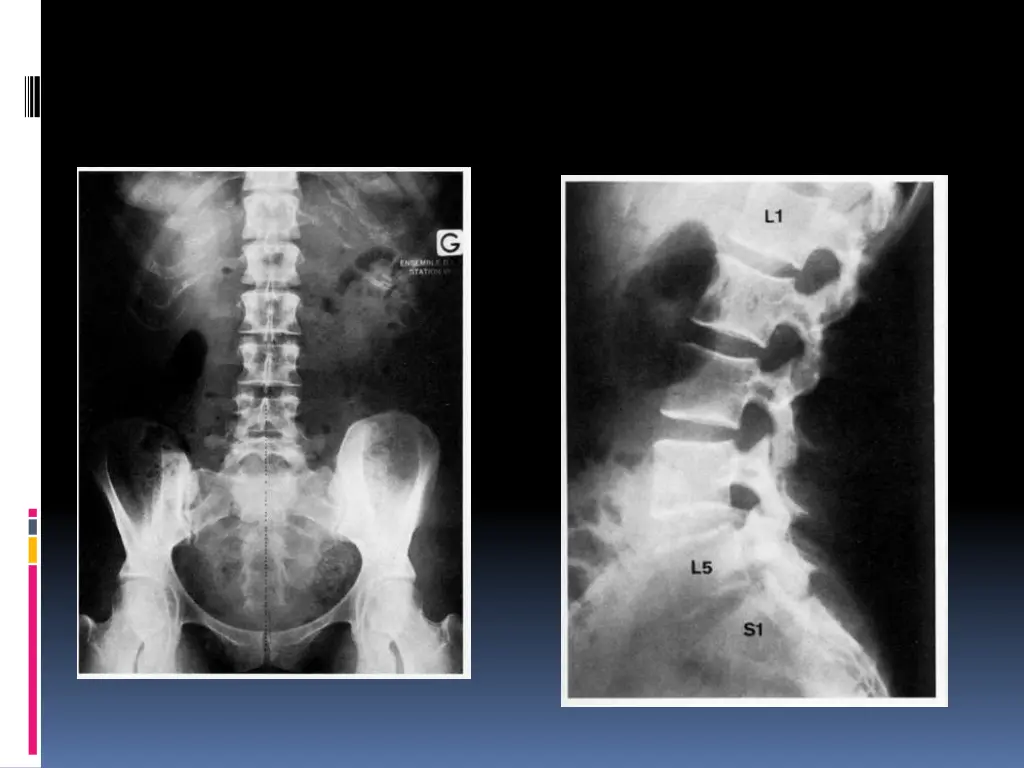

Examens complmentaires Interrogatoire + examen clinique=== diagnostic de sciatique commune Minimum : Un bilan inflammatoire Radiographies standards Incidences : -bassin de face debout (articulations sacro-iliaques,articulations coxo- f morales et du sacrum -rachis lombaire face + profil (statique, anomalie transitionnelle, qualit de l os,analyse des disques dont la hauteur peut tre diminu e, d veloppement arthrosique